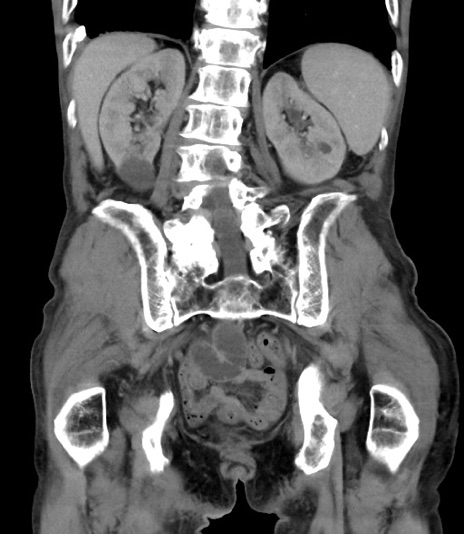

症例3(冠状断像)

【症例】 70歳代男性

【主訴】右鼠径部腫瘤、疼痛

【現病歴】本日朝より上記主訴あり、受診。

【既往歴】膀胱癌にて膀胱全摘、両側尿管皮膚瘻

【データ】WBC 5600、CRP 0.56